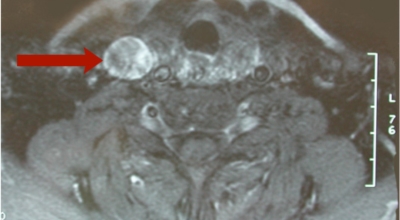

갑상선항진증이 의심되면 혈액검사를 통해 혈액내 호르몬 농도를 측정해 진단할 수 있는데 항진증 환자는 혈액 내 호르몬 농도가 높게 나타나며, 갑상선 자극 호르몬은 낮게 나타나요. 또한 보다 정확한 진단과 원인을 알기 위해서 갑상선 항체검사, 초음파, 스캔을 하는 방법이 있습니다. 또한 갑상선기능항진증의 치료방법으로는 첫 번째 항갑상선 약을 섭취하는 방법이 있어요.